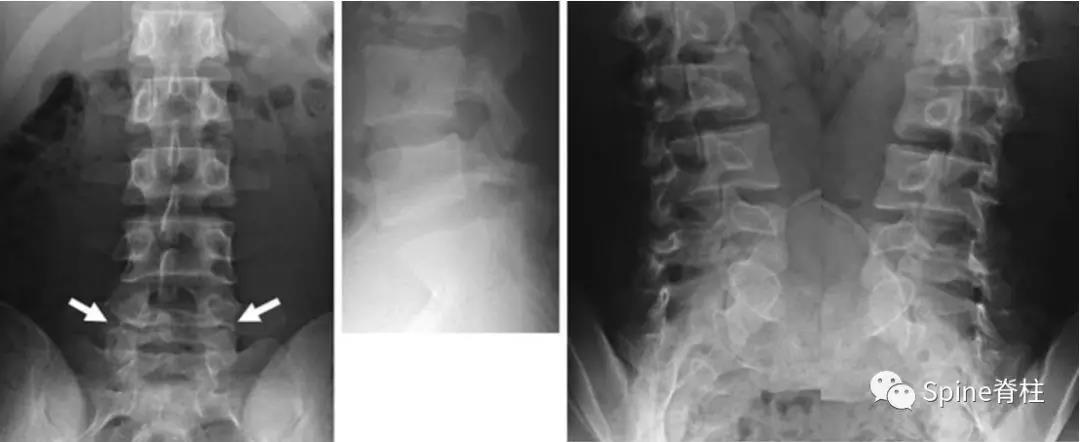

图:6个月复查可见右侧椎弓根裂已愈合(单箭头),但出现右侧峡部裂(双箭头)